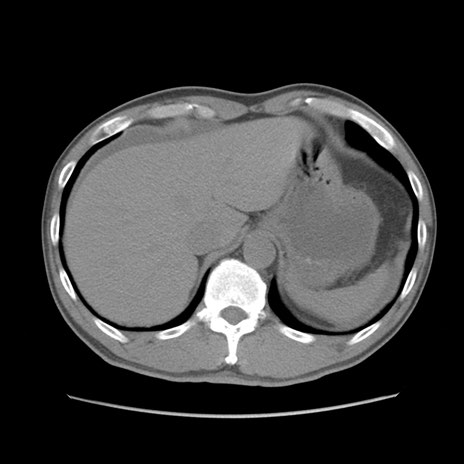

症例56 CT(横断像)

脂肪ウインドウ